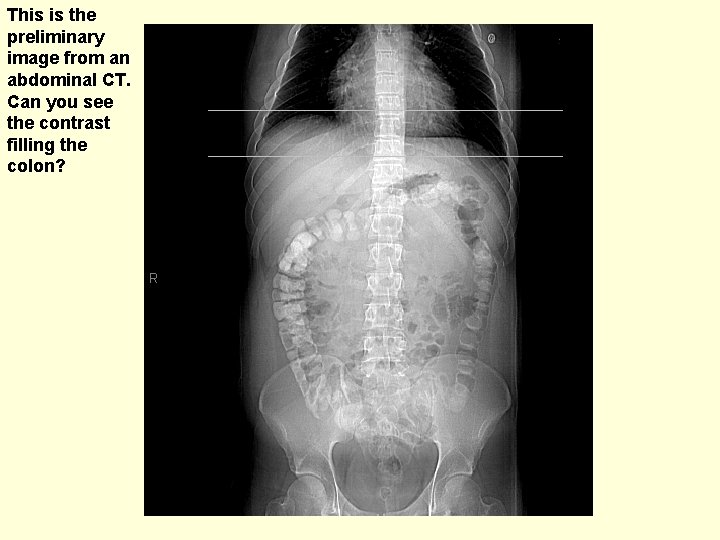

This is the preliminary image from an abdominal CT. Can you see the contrast filling the colon?